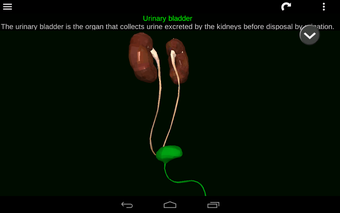

Diese Anwendung zeigt ein dreidimensionales Modell der menschlichen Körperorgane und eine Beschreibung aller von ihnen.

Sie können jedes Organ wie Herz, Gehirn, Lunge, Fortpflanzungssystem, Leber, Darm, Eierstock, Hoden, Magen, Niere usw. anfassen.

Sie ist für alle Menschen nützlich, auch für Studenten, da jedes Anatomieorgan in einer anderen Farbe dargestellt ist.

Sie können die App verwenden, um herauszufinden, welches die verschiedenen Körperorgane sind und welche Funktionen sie haben.